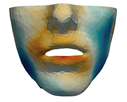

3.3. Simulation Error and Performance

- Segmentation of the maxilla and mandible. For all patients, the highest error (except for the neck, which is not clinically relevant as discussed above) appears near the cut areas, both of the maxilla (e.g., patients M5 and M7) and the mandible (e.g., patients M1 and M3). This is probably due to the presence of fixation plates and/or bone grafts in the real result (e.g., patient M10, whose maxilla was not segmented, but where the presence of bone graft has been confirmed by the surgeon who carried out the intervention). As a consequence, patients with a segmented maxilla and/or mandible show in general larger error than those without segmented bones. However, the smooth coupling method proposed in Section 2.3.3 reduces considerably the error in cut areas, as shown in Figure 2.

4.3. Comparison of Fine and Coarse Meshes